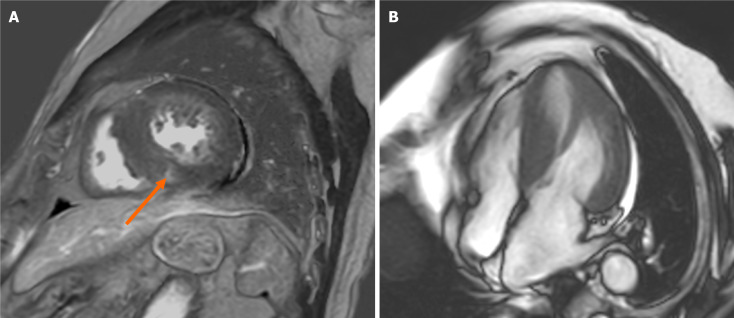

Results: Among 19 patients experiencing OHCA, 7 experienced it in trains or on railway platforms, 4 while practicing sports, and 4 during their daily work. Ten of the 19 survivors were diagnosed with coronary vasospasm (CVS), in whom CMR failed to depict its characteristic findings. CMR was useful for identifying myocardial damage associated with hypertrophic cardiomyopathy (HCM) or myocardial infarction (MI). LGE was related to serious ventricular arrhythmias after implantable cardioverter defibrillator (ICD) installation in 3 patients (CVS, 2; HCM, 1).

Conclusion: CMR is useful for identifying myocardial damage of HCM or MI inducing OHCA and predicting ventricular arrhythmias after ICD implantation but has limited capability for detecting myocardial damage of CVS.